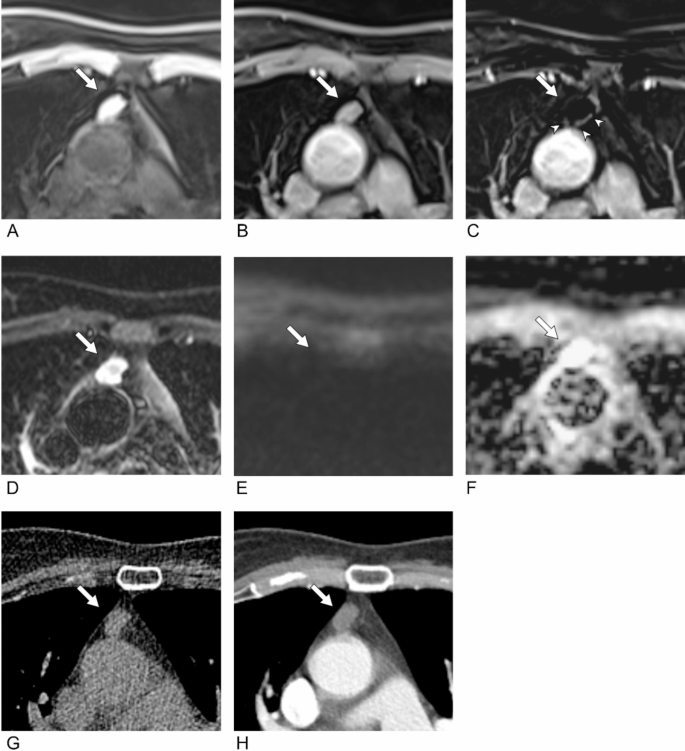

Based on the results in the reading set from Institution A, Session 5 at institution B consisted of the same combination of MR sequences as Session 3. The inter-reader agreement was fair (κ = 0.37) for the three-category scale and moderate (κ = 0.48) for the two-category scale (Table 2, Supplementary Table 3). After adding CT, the inter-reader agreement increased to moderate (κ = 0.53) for the three-category scale and substantial (κ = 0.74) for the two-category scale despite; however, these findings were not statistically significant (p = 0.227 and 0.241, respectively) (Fig. 4).

Example of improved agreement with addition of CT in the external reading set in a 67-year-old woman. (A) A pre-contrast T1WI demonstrated a 17-mm nodule with internal T1 hyperintensity in the anterior mediastinum (arrow). (B) No internal enhancement is present on post-contrast T1WI, but (D) the subtracted image demonstrated eccentric enhancing wall thickening (arrowheads) on the left side of the nodule. (D) The nodule showed T2 hyperintensity. (E, F) The DWI/ADC maps did not show diffusion restriction. However, one reader (Reader 1) was suspicious of eccentric wall thickening on the subtracted image and thus diagnosed the nodule as indeterminate for a cyst, whereas the other three readers diagnosed the lesion as a definite cyst. After the addition of CT (G, H), all readers, including Reader 1, diagnosed the lesion as a cyst based on the lack of enhancement on the post-contrast CT image (H) and the consistent low attenuation of the lesion on both pre- and post-contrast CT.